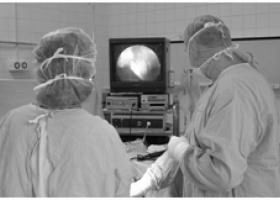

Однак найбільш інформативним способом вважається діагностична лапароскопія, що дозволяє візуально виявити захворювання, і в разі потреби взяти матеріал для гістологічного аналізу. Обстеження проводиться за допомогою оптичного устаткування. При виконанні процедури на передній стінці очеревини робляться невеликі проколи, через які в черевну порожнину вводиться апарат.

- Хірургічне лікування проводиться, як правило, лапароскопічним методом. Сьогодні така операція вважається -Золота стандартом- в лікуванні завдяки мінімальній травматизації стінки очеревини. Більш того, при цьому методі ризик утворення спайок в малому тазі зведений до мінімуму. Кіста разом з капсулою видаляється через отвір в передній черевній стінці. Під час щадного видалення пухлини вдається домогтися максимального збереження здорової тканини яєчника у жінок репродуктивного віку. У разі, якщо утворення великих розмірів і відсікти його від здорових структур не завжди можливо, проводиться видалення яєчника.